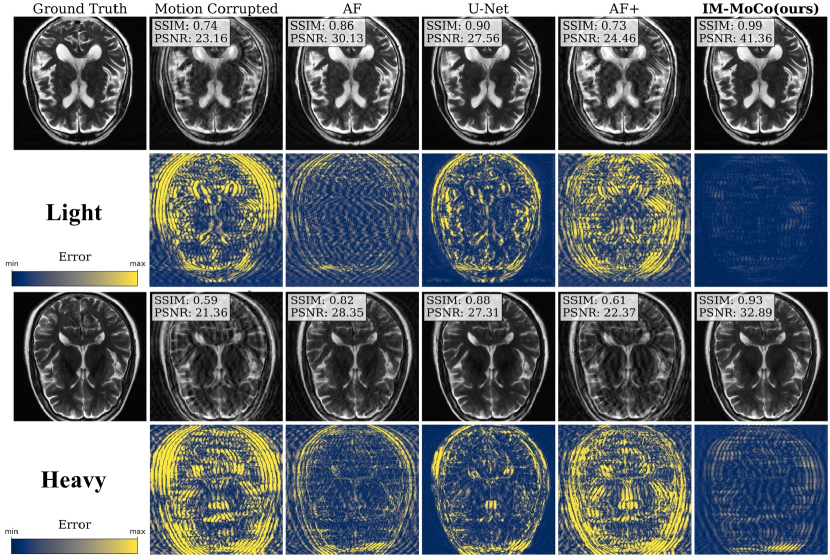

Refer to caption

Figure 4: The visualization shows the worst results of motion-corrected images of our IM-MoCo pipeline besides motion-corrupted, ground truth, and comparison methods. The first and third rows show the light and heavy correction results, respectively. The second and fourth rows show the residual error images.

Figure 5: The visualization shows the best results of motion-corrected images of our IM-MoCo pipeline besides motion-corrupted, ground truth, and comparison methods. The first and third rows show the light and heavy correction results, respectively. The second and fourth rows show the residual error images.